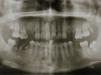

The patient underwent additional imaging, in which (panoramic radiograph: Fig. 2) a communication between the root tips and maxillary sinus was suggested. Computed tomography (CT), acquired with GE Healthcare Light Speed Ultra Pro® (EUA), revealed a low-density and well-circumscribed lesion occupying the entire left maxillary sinus.

The coronal slice of the CT showed the right and left maxillary sinus completely filled. On the left maxillary sinus, the loss of the alveolar cortical bone in correspondence with the root fragments region and, therefore, a direct communication between the oral cavity and the maxillary sinus was also evident. In this location we could also identify an encapsulated lesion, opacification and fluid. On the right side of the maxillary sinus, the CT slice exposed the presence of teeth with apical periodontitis, a severe mucosal thickening, fluid and opacification (Fig. 3). The axial slice of the CT showed a new cortical alveolar bulging, probably as a result of the cystic lesion and was also related with the facial asymmetry. The CT sagittal slice confirmed the presence of the oro-antral fistula.